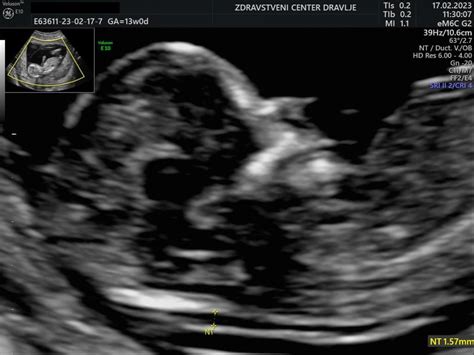

- 11. do 14. teden nosečnosti: Ta pregled je namenjen presejanju za kromosomske nepravilnosti. Vključuje ultrazvočno merjenje nuhalne svetline (NS), ki je debelina nabrane tekočine na zatilju ploda, ter oceno nosne kosti. Povečana NS ali odsotna/slabo razvita nosna kost lahko nakazujeta na povečano tveganje za kromosomske nepravilnosti, kot je Downov sindrom. V tem obdobju se lahko opravi tudi dvojni hormonski test (DHT), ki skupaj z ultrazvočnimi meritvami poveča zanesljivost odkrivanja kromosomskih nepravilnosti na približno 90%. Za natančnejše določanje tveganja se lahko uporabi tudi neinvazivni test proste plodove DNA (NIPT), ki z 99,3% zanesljivostjo odkrije najpogostejše kromosomske nepravilnosti. Če se pri teh presejalnih metodah izkaže visoko tveganje, se lahko opravijo invazivne diagnostične preiskave, kot sta biopsija horionskih resic (BHR) ali amniocenteza.